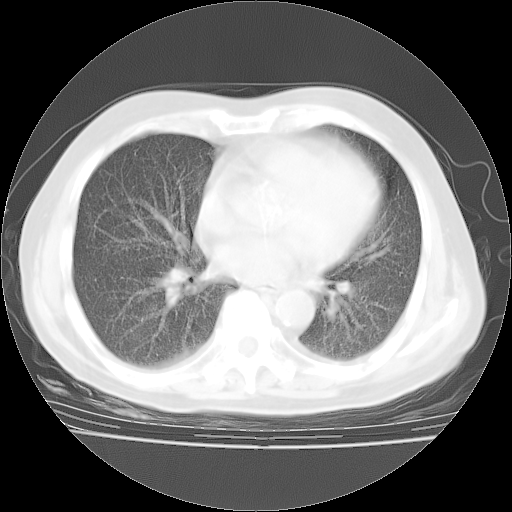

4月28日肺部CT——再次出现类似去年5月9日——透光度降低,“间质性”改变。

4月28日肺部CT——再次出现类似去年5月9日——磨玻璃样、间有“粟粒样”改变。

个人阅读4.14日肺部CT平扫:纵隔窗无异常,但肺窗示:双下肺内、后基底段有片絮状侵润影,部位以后基底段为著,以间质改变为主,呈急性肺泡炎征像,和首次住院影像学有相似之处。仅是个人读片,明日请相关专家再读片哈。其它建议同上。

1、108#的是4月14日的胸部CT(发此贴时还没看着28日的CT)。14日的胸部CT其实已经出现改变(如108#所述),个人认为28日的胸部CT除纵膈窗疑似有双侧胸膜增厚或少量胸积液(可行胸部B超明确)外,与4月14日对照病变有所加重;2、已经给予“异烟肼、利福平、乙胺丁醇”抗痨治疗?如果是,甲强龙80mg可缓慢减量;如果环磷酰胺已停用,暂不使用;3、中性粒细胞92%,明显升高,目前体温情况?注意合并细菌感染可能,使用左氧氟沙星情况下,是否联用B-内酰胺类抗菌药物?另外是查免疫全套非风湿全套。

今请临免主任会诊后认为:4月14日胸部CT已有双下肺间质性改变。患者病情复发多系激素减量过快不正规所致。目前甲强龙80mg/日,一周后酌情开始减量,不易过快。环磷酰胺若已停用,暂不使用。他同意目前抗菌药物使用,但应考虑是否加用B-内酰胺类抗菌药物(中性细胞明显增高);2、结核复发目前依据不足;3、若免疫全套各项指标正常,考虑多系特发性肺间质炎可能大。4、加强支持,并注意保护胃黏膜。

今上午去请教了临免、呼吸主任:1、介绍病史和阅读系列胸部CT一致认为:患者肺结核不考虑,仍为肺间质纤维化,目前处于急性肺泡炎阶段。2、若仍发热,可将甲强龙增至:80mg Bid静滴,同时鉴于中性增高,合并细菌感染可能,继续左氧氟沙星治疗,再联用B-内酰胺抗菌药物,如头孢哌酮--舒巴坦;3、停用抗痨药;4、目前甲强龙每日剂量160mg ,体温正常后再酌情减量;目前暂不用免疫抑制剂;4、不建议使用免疫增强剂等;5、加强支持治疗,鼓励患者进食;5、注意随访肝、肾功及血常规情况;6、因患者目前激素用量较大,加用胃黏膜保护剂,防止消化道出血可能。